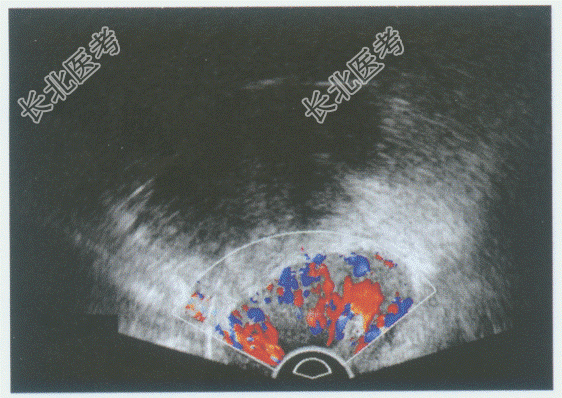

- 单项选择题临床资料:女性患者, 32岁,自述不规则阴道出血半月余。超声综合描述: (图1经腹扫查;图2、彩图经阴道扫查)子宫颈形态失常, 宫颈后唇可见低回声区,边界尚清晰, 形态规则,向外突起, CDFI:其内可见丰富动静脉血流信号。